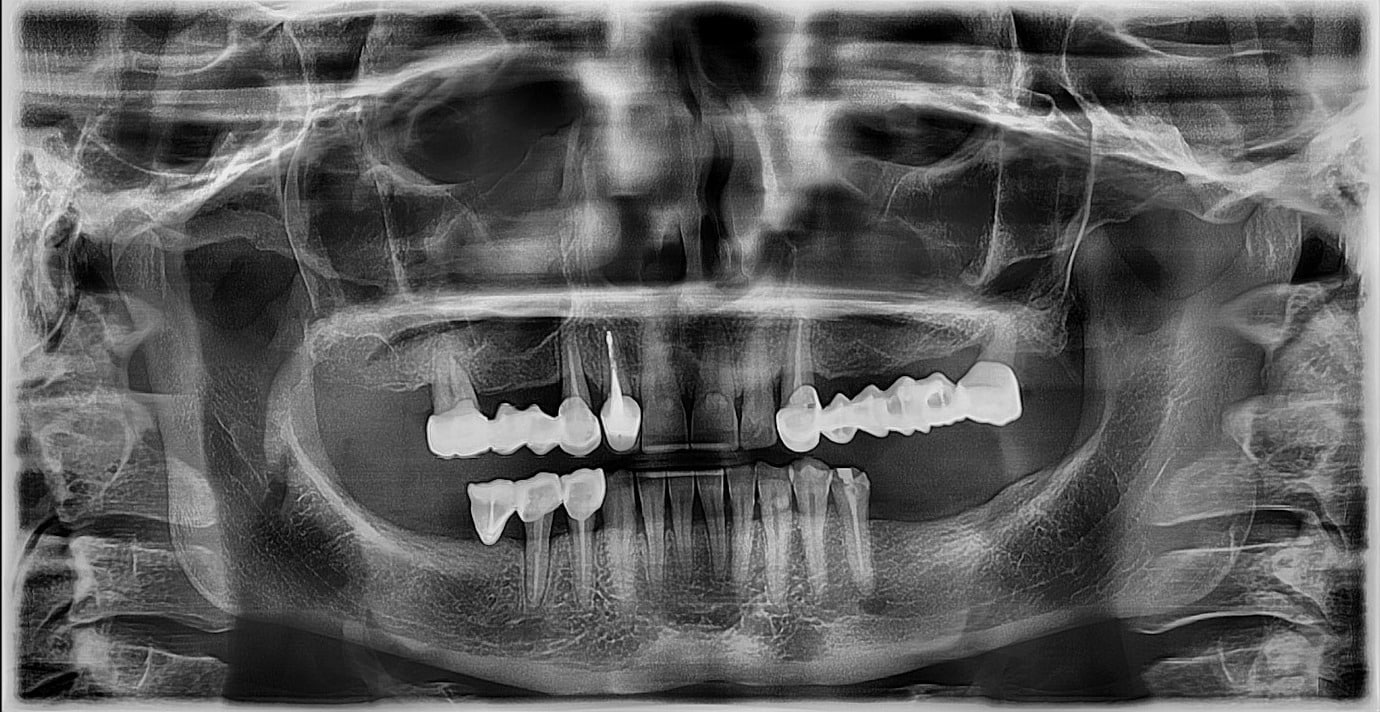

Pacienta s-a prezentat în cabinet pentru a proteza pe implanturi edentația din cadranul III. în urma evaluării clinice și radiologice s-a recomandat schimbarea tuturor lucrărilor protetice.

Planul inițial a fost extracția dinților 16 și 28 și inserarea implanturilor în pozițiile 14, 15, 17, 24, 26, 27.

În urma evaluării CBCT-ului s-a constatat necesitatea realizării augmentarii osoase ăn zona posterioară maxilară, lifting sinusal maxilar bilateral odată cu inserarea implanturilor.

Preoperator, s-au îndepărtat lucrările protetice maxilare și s-a hotarat extracția dinților 12, 13.